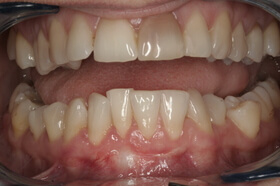

Agresszív fogágybetegség miatt kialakult frontfog elmozdulás – elülső nézet